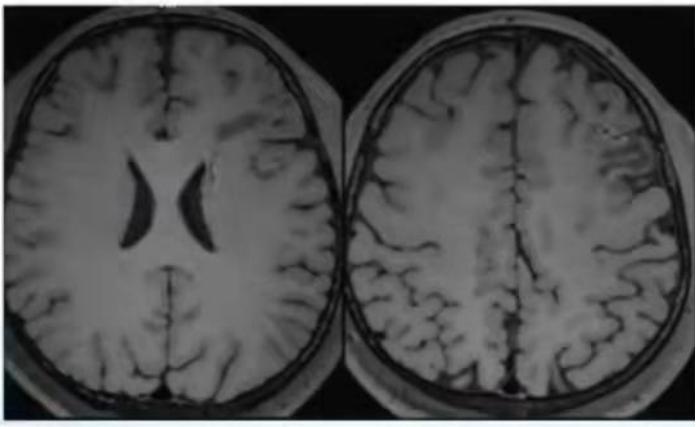

2021年1月复查头颅MRI提示:左侧额顶叶梗死病灶(见图1),DSA提示夹层已经消失(见图2)。

图1:头颅MRI平扫

图2:DSA患者抗凝效果佳,复查颈内动脉夹层消失后,改用了阿司匹林+阿托伐他汀二级预防。